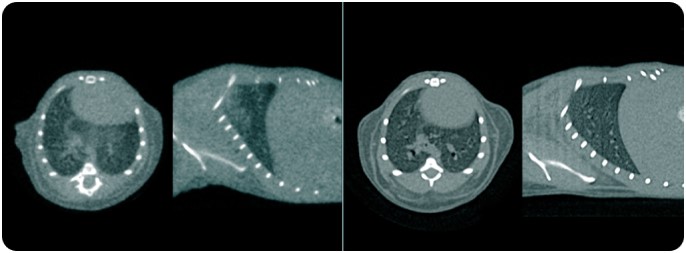

CT Features

• 52 µm resolution

• 80 (200) x 80 mm FOV single (multiple) bed positions

• Gated cardiac imaging

• Patented 2-5 x dose reduction